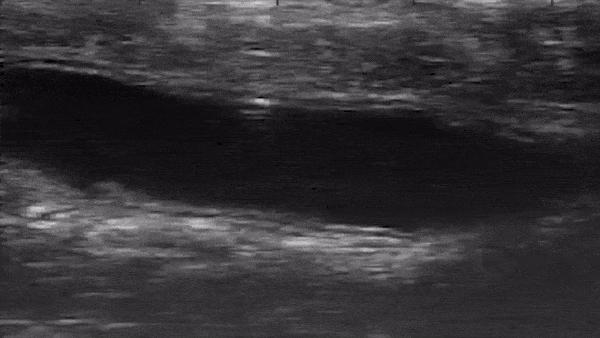

image: Live ultrasound footage shows a microrobot tumbling through a colon in vivo.

The team conducted the in vivo experiments in the colons of live mice under anesthesia, inserting the microrobot in a saline solution through the rectum. They used ultrasound equipment to observe in real time how well the microrobot moved around.